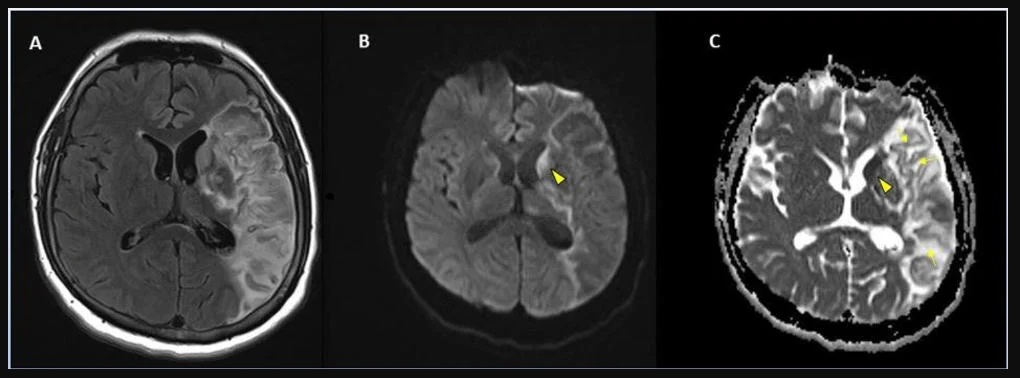

This photo gallery shows the variety of radiological presentations of COVID-19 (SARS-CoV-2) in medical imaging, including computed tomography (CT), radiograph X-rays, ultrasound, echocardiograms and magnetic resonance imaging (MRI). The radiology images show examples of typical COVID pneumonia in the lungs and the numerous complications the virus causes in the body in multiple organs, including the brain, kidneys, heart, abdomen and vascular system.

Ultrasound, especially hand-held ultrasound imaging devices, have become a primary imaging modality for novel coronavirus because of the ease to bag the device and sterilize it after use. CT and mobile X-ray systems are also used as front-line imaging systems for COVID-positive or suspected COVID patients.